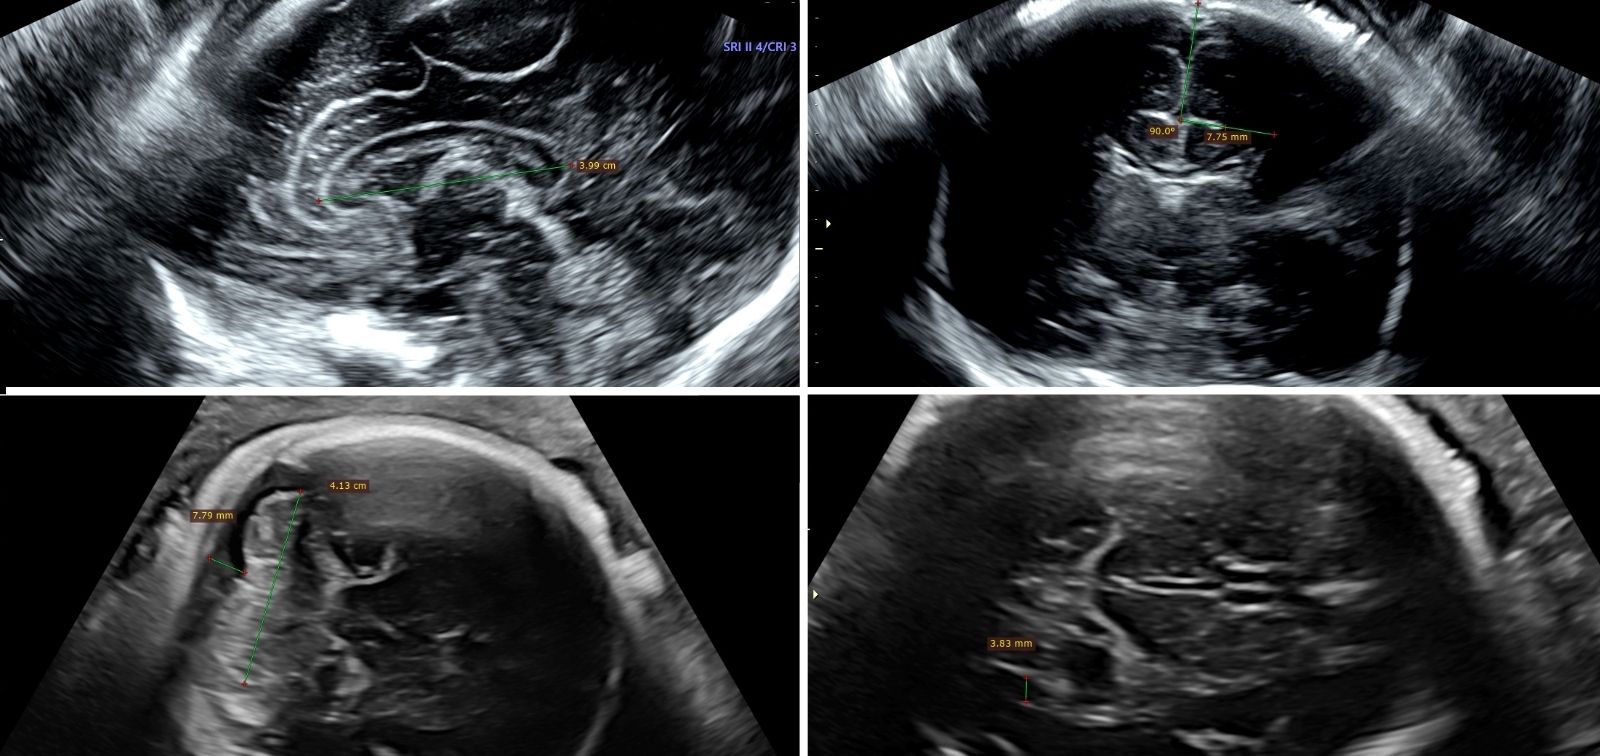

During the third trimester of pregnancy, participants underwent transvaginal neurosonography, a specialized ultrasound that allows the analysis of fetal brain shape and structures. Exposure to nitrogen dioxide (NO₂), particulate matter (PM2.5), and black carbon was estimated with hybrid models that combine data from real measurements with advanced statistical methods. The research considered three “microenvironments”: the participants’ homes, workplaces, and commuting routes. Data on activity patterns were collected via a geolocation app installed on the participants’ mobile phones.

The research team observed that prenatal exposure to NO₂, PM2.5, and black carbon in all aforementioned microenvironments combined was associated with an increase in the volume of various brain cavities that contain cerebrospinal fluid. Specifically, direct associations were identified between exposure to these pollutants and increased volume of the lateral ventricles, located in each brain hemisphere, as well as an enlargement of the cisterna magna, a cavity located at the lower part of the brain. An increase in the width of the cerebellar vermis —the central part of the cerebellum, essential for balance and motor coordination— was also detected.

The study results also showed an association between higher exposure to black carbon and a reduction in the depth of the lateral sulcus (also known as the Sylvian fissure), a deep groove that runs through the brain, which might suggest less maturation of the brain.